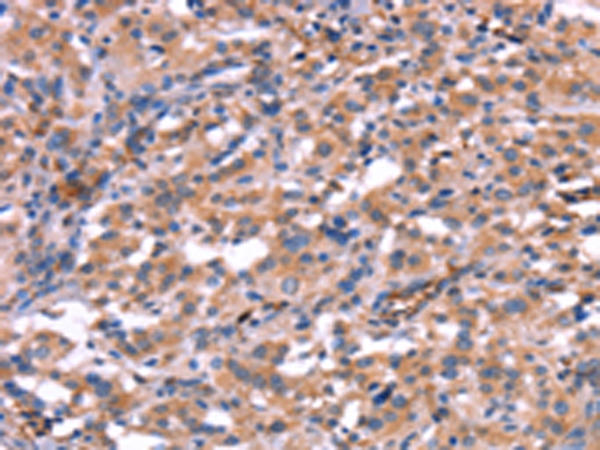

分类: 科研抗体货号: P04969别名: IMB1; IPO1; IPOB; Impnb; NTF97应用: IHC反应种属: Human, Mouse, Rat